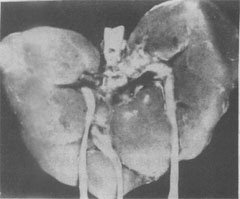

(2)Edwards综合征:染色体异常为18三体。表型特征有智力低下、小头、前额窄、枕部突、小颌且张口范围小,腭弓高窄、低位耳、肾畸形(图6-3)、肌张力增高及手紧握等(图6-4)。

图6-3 18三体(Edwards)综合征的畸形肾

图示马蹄状融合肾及额外输尿管